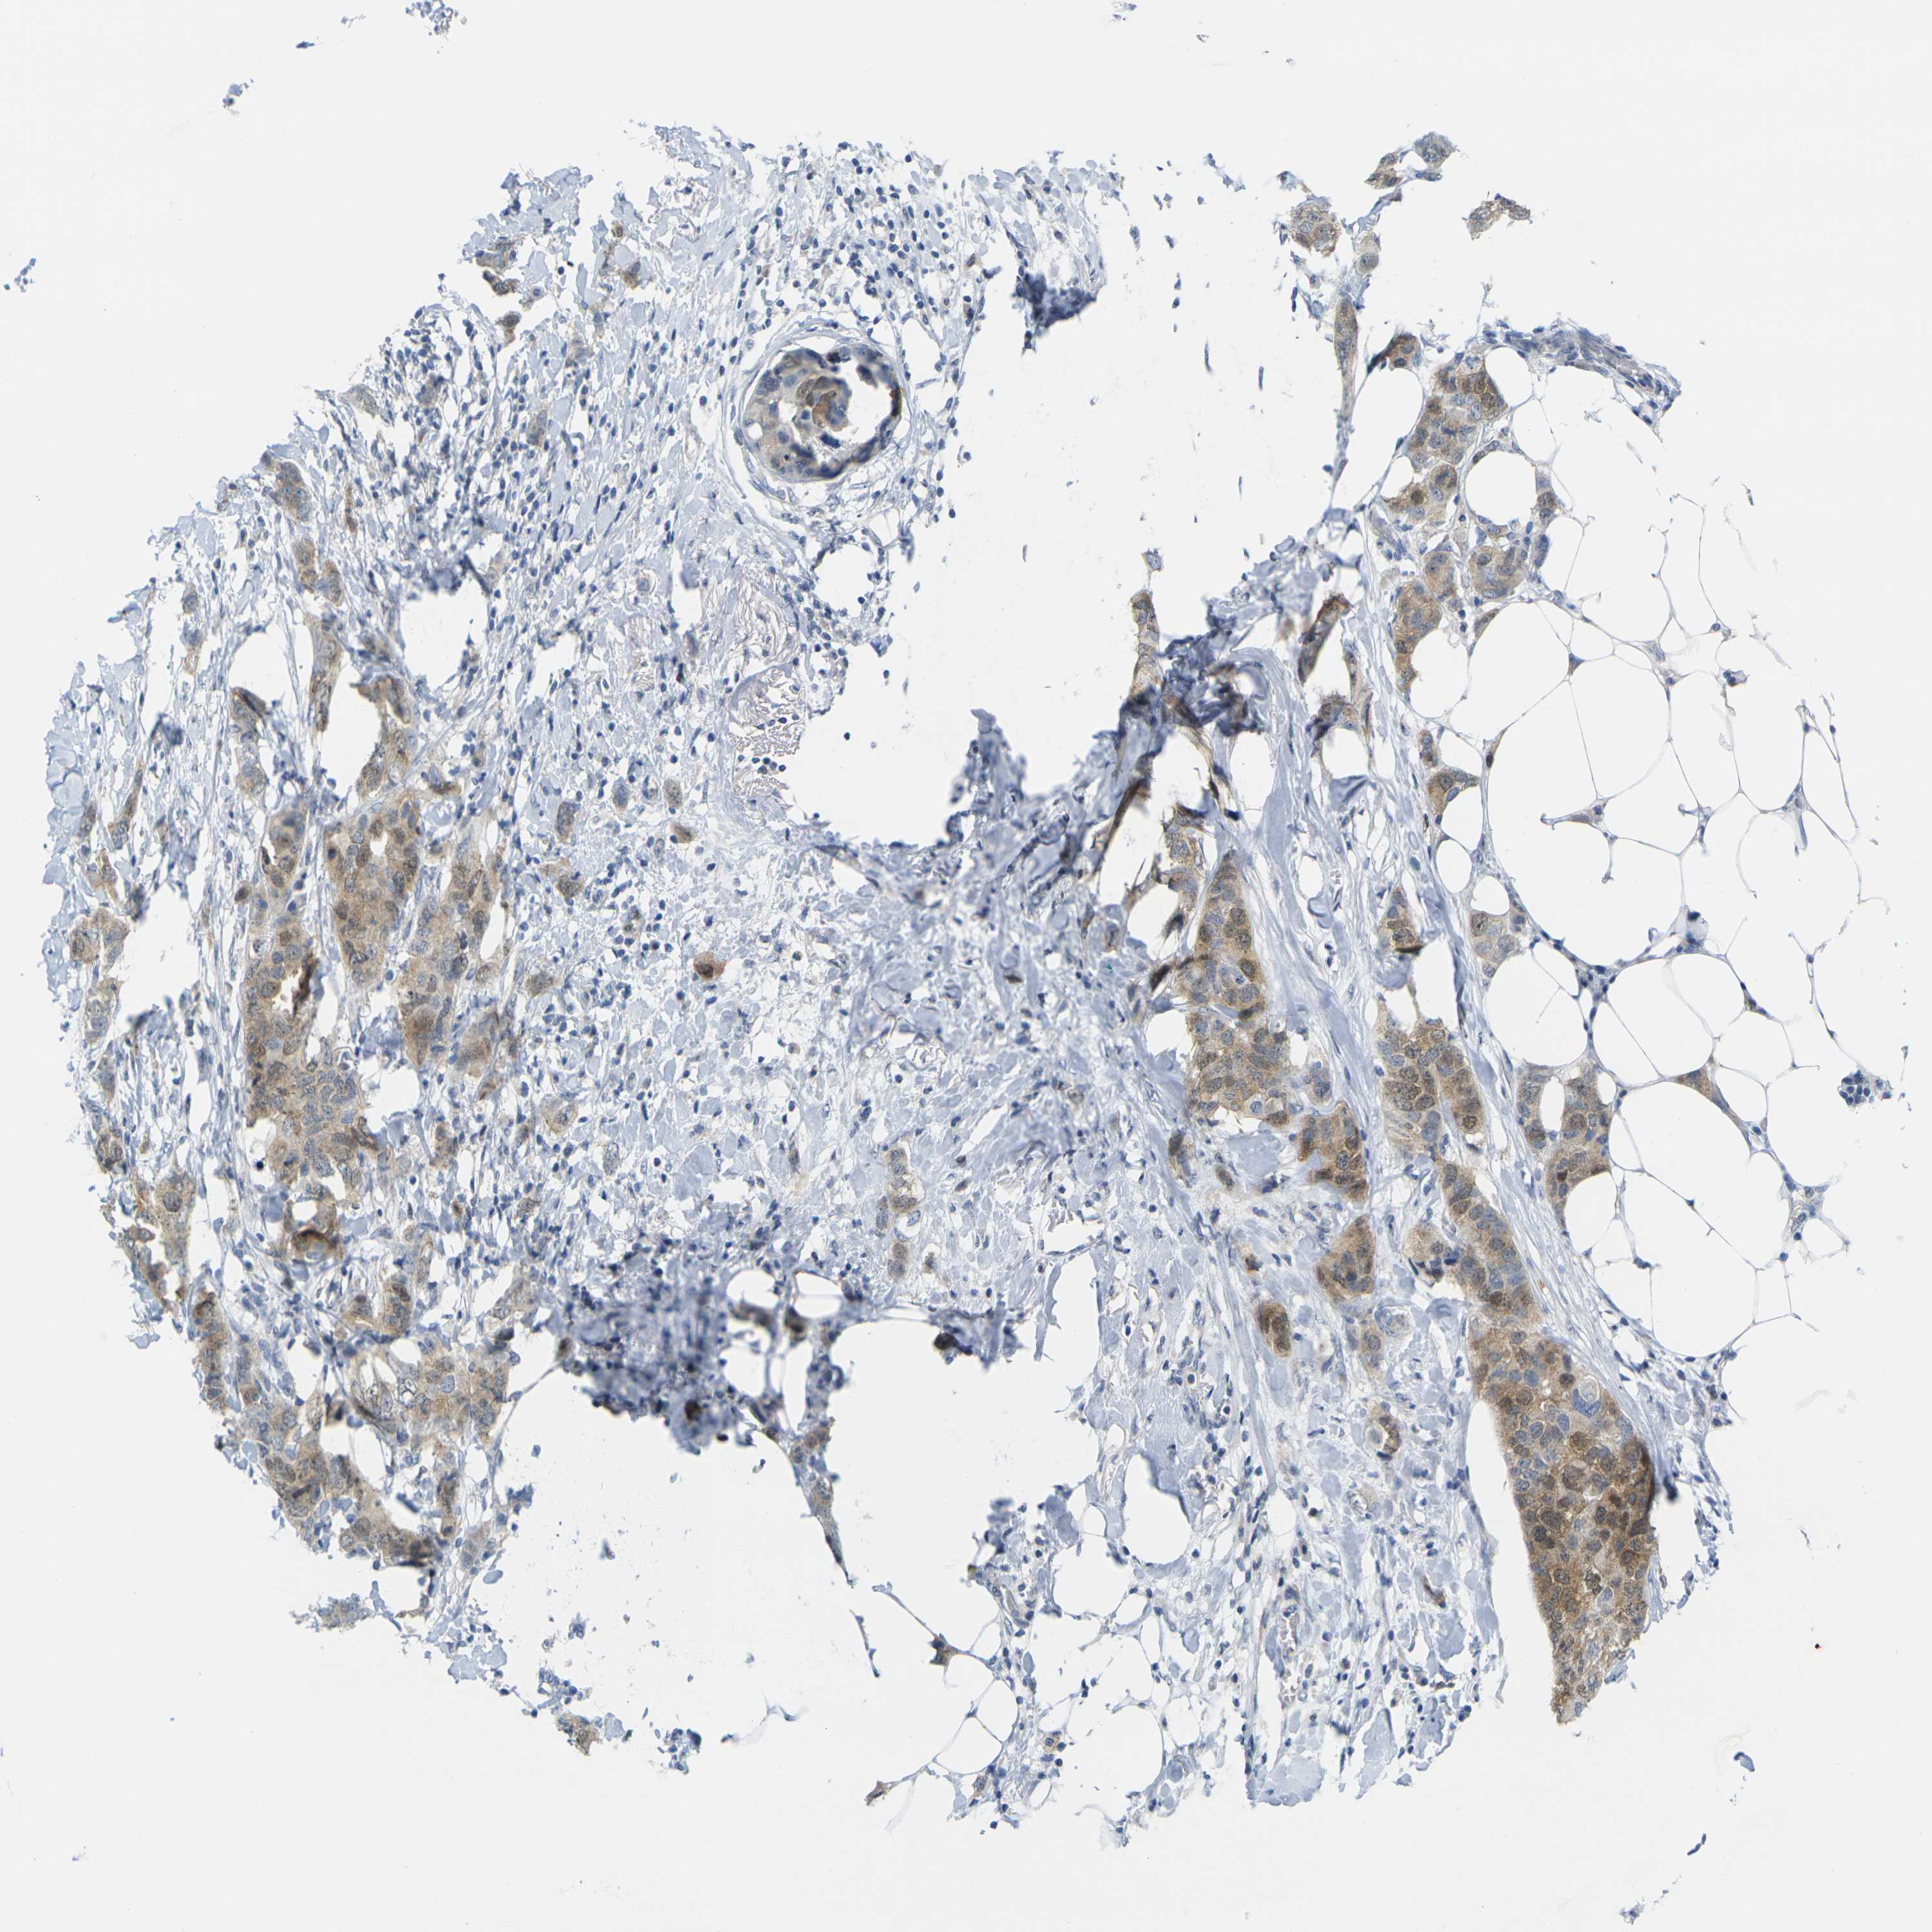

BRCA TCGA BRCA VALIDATION PROTEIN EXPRESSION

ANTIBODIES

AND

VALIDATION